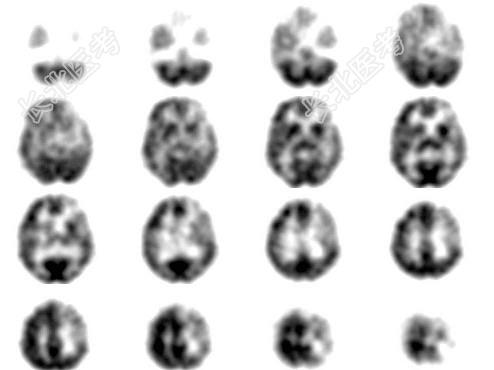

- 单项选择题女性患者56岁,突发黑朦2h, 无头疼及意识障碍,行99Tcm-ECD脑血流断层显像及CT扫描如图, 诊断为 ( )

C、左侧额叶、顶叶、颞叶TIA

D、左侧额叶、顶叶脑梗死

E、左侧大脑半球癫痫